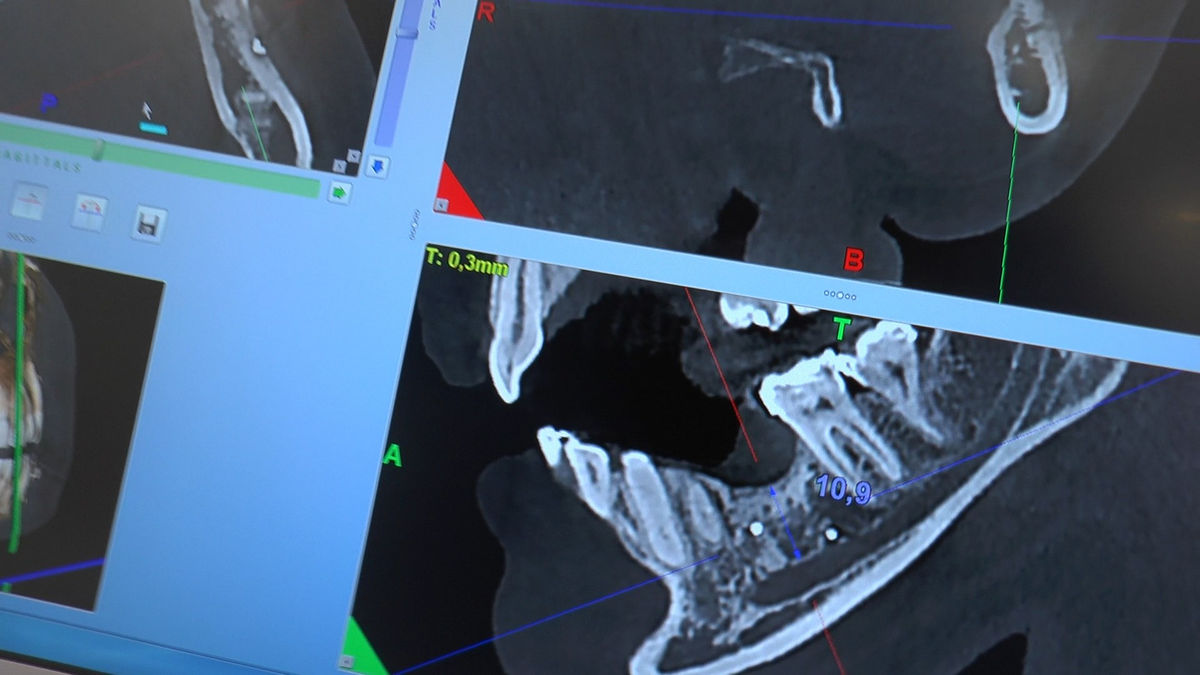

Practiculum Implantologii – Sezon V/B, sesja 8, część 4